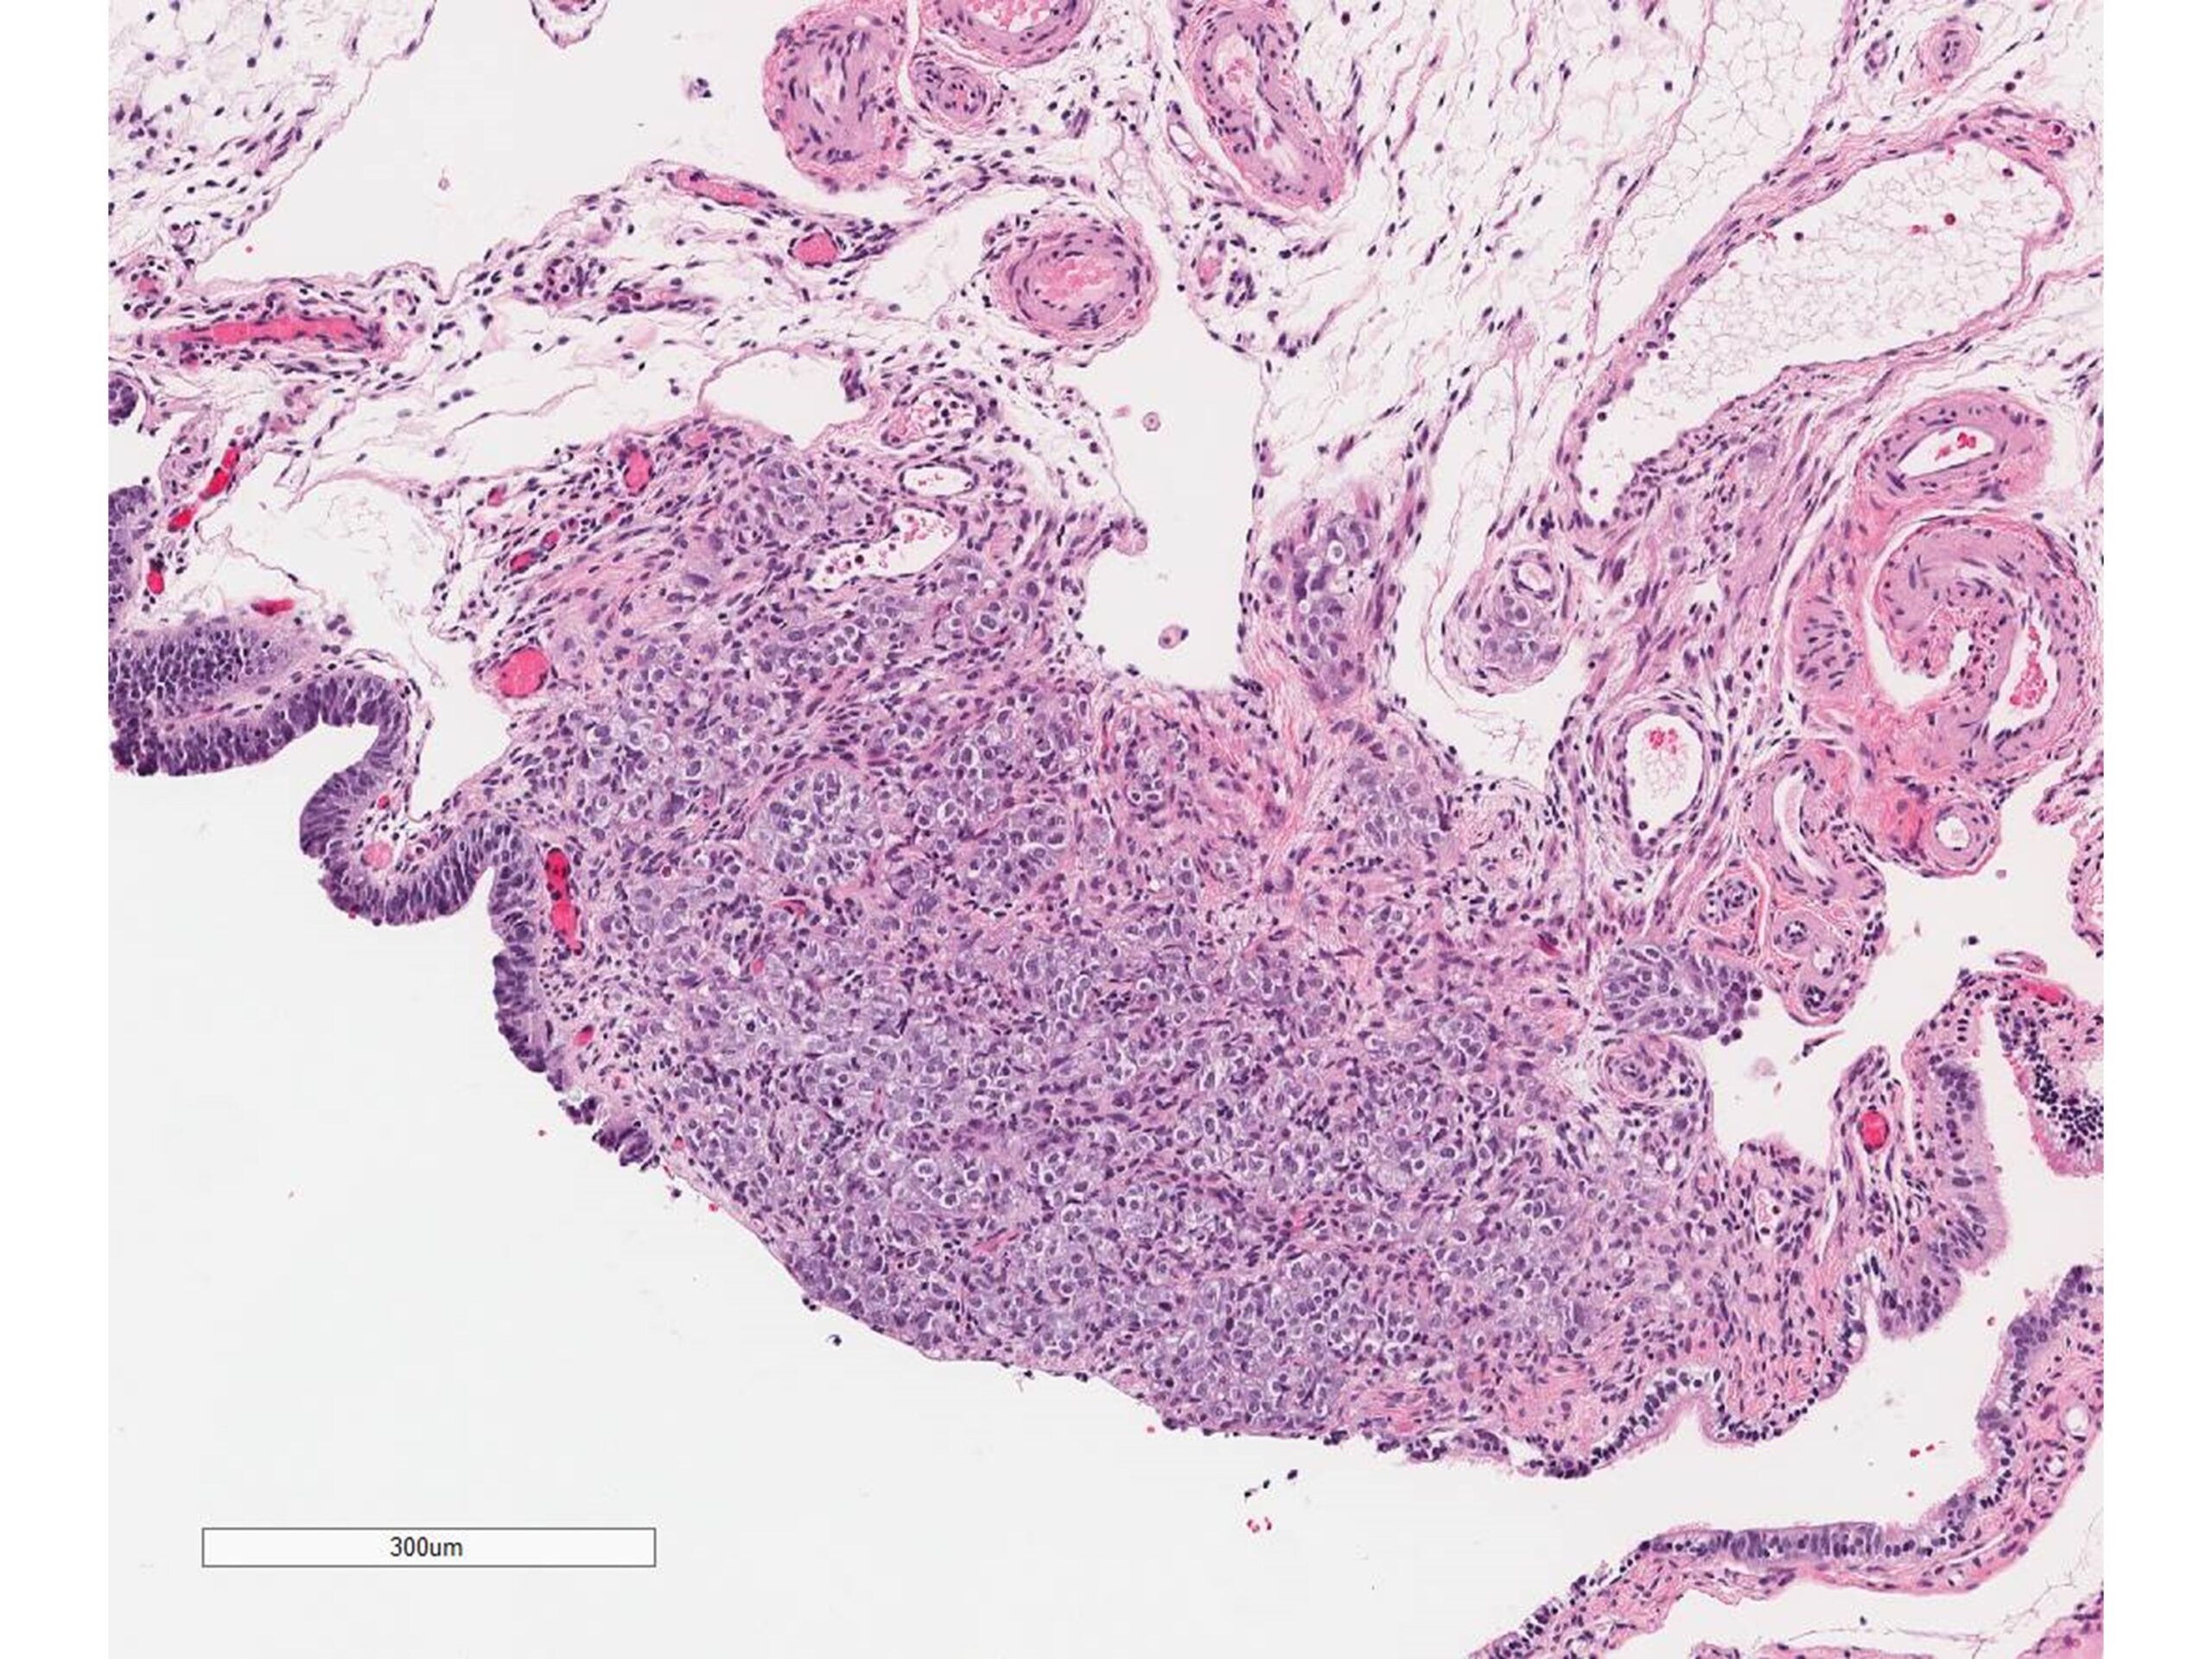

Germline pathogenic variants in BRCA1 or BRCA2 genes increase the risk of ovarian high grade serous carcinoma, the most common and most lethal subtype of epithelial ovarian cancer. Carriers of these genetic variants are usually offered surgery known as risk-reducing salpingo-oophorectomy (RRSO) where the Fallopian tubes and ovaries are removed. We report the case of a woman carrying a germline pathogenic variant in BRCA1 who received RRSO but developed peritoneal cancer 15 years later. We reveal through DNA sequencing and analysis that the peritoneal cancer is a recurrence of a Fallopian tube cancer that was missed on initial pathologic examination. (By Drs. Setor Amuzu, Lili Fu, and William D Foulkes, https://jmg.bmj.com/content/early/2022/01/16/jmedgenet-2021-108269 )